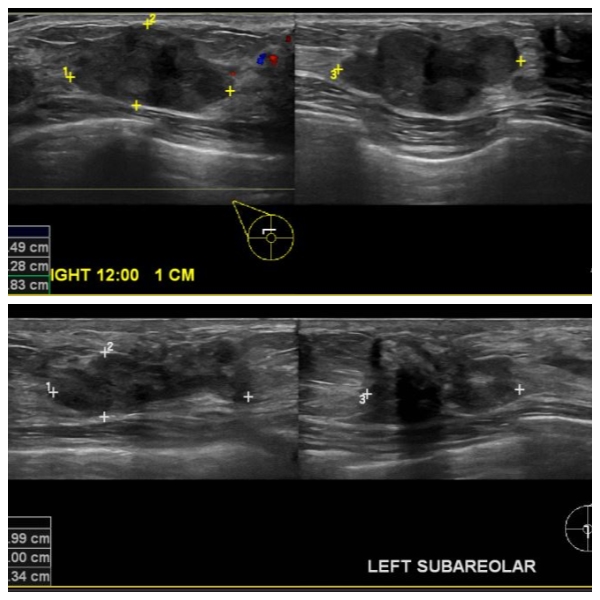

건강검진상 이상소견 있어 내원하신 53세 여자분으로 우측유방 12시방향 1CM떨어진 곳과

좌측유방 유두 및을 조직검사한 후 양쪽유방 유관암 진단되셨습니다.